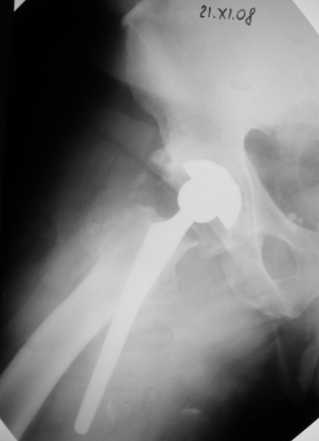

Сегодня свершилась ревизия. С максимально бережным отношением к тканям выделил бедро.

Ножка "слету " удалить не удалось, после выделения долотом ножку удалил.

Поставил Corail большего размера.

Рентгенограммы вывешу.